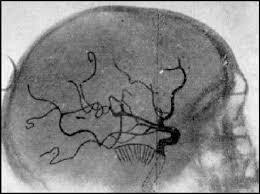

• Egas Moniz.

Médico Neurólogo. Fundador de la moderna neurocirugía. Pionero en la técnica de angiografía, permitiendo examinar las arterias del cerebro mediante Rayos X